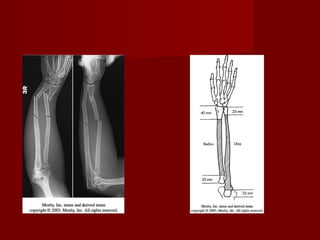

Fractura-luxación del tercio distal del

radio con luxación de la articulación

radio-cubital distal(fractura-luxacion de

Galeazzi)

   La fractura inevitable.

   El tratamiento mediante

reducción      cerrada  e

inmovilización con yeso

tiene una alta taza de

fracaso.

   La reducción abierta y

fijación con placa de

compresión 3.5 es el

método de elección.

   Si aún después de fijar el

radio, la luxación radio

cubital es inestable, se

debe fijar con pines

Kirschner.